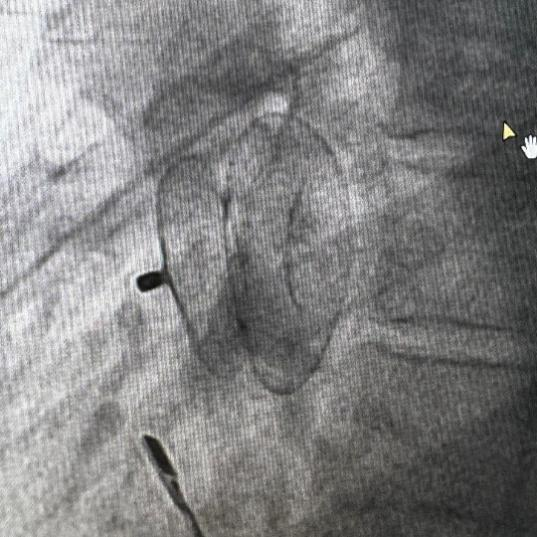

我院心脏外科微创团队李永超医师在熟悉外科手术的基础上,进修学习了介入封堵技术,接触和实践了大量房缺、卵圆孔未闭的封堵手术,从外科医生的视角更好的了解了这类技术。在心脏介入专家刘元伟教授的悉心指导和心内超声帮助下,我院心脏外科微创团队的李永超医师,携刘耀荣、韩雪松两位助手,在透视下依次释放封堵器的左房伞和右房伞,完全释放封堵器后,心内彩超未见残余左房向右房分流,手术顺利完成。心脏外科微创团队依托于北京清华长庚医院心血管中心,以患者为中心,联合优势力量,破除了内科医生和外科医生的界限,为患者选择最佳治疗方式。本次手术的成功充分体现了内外科医生联合的优势,也最大限度的保证了手术安全性。